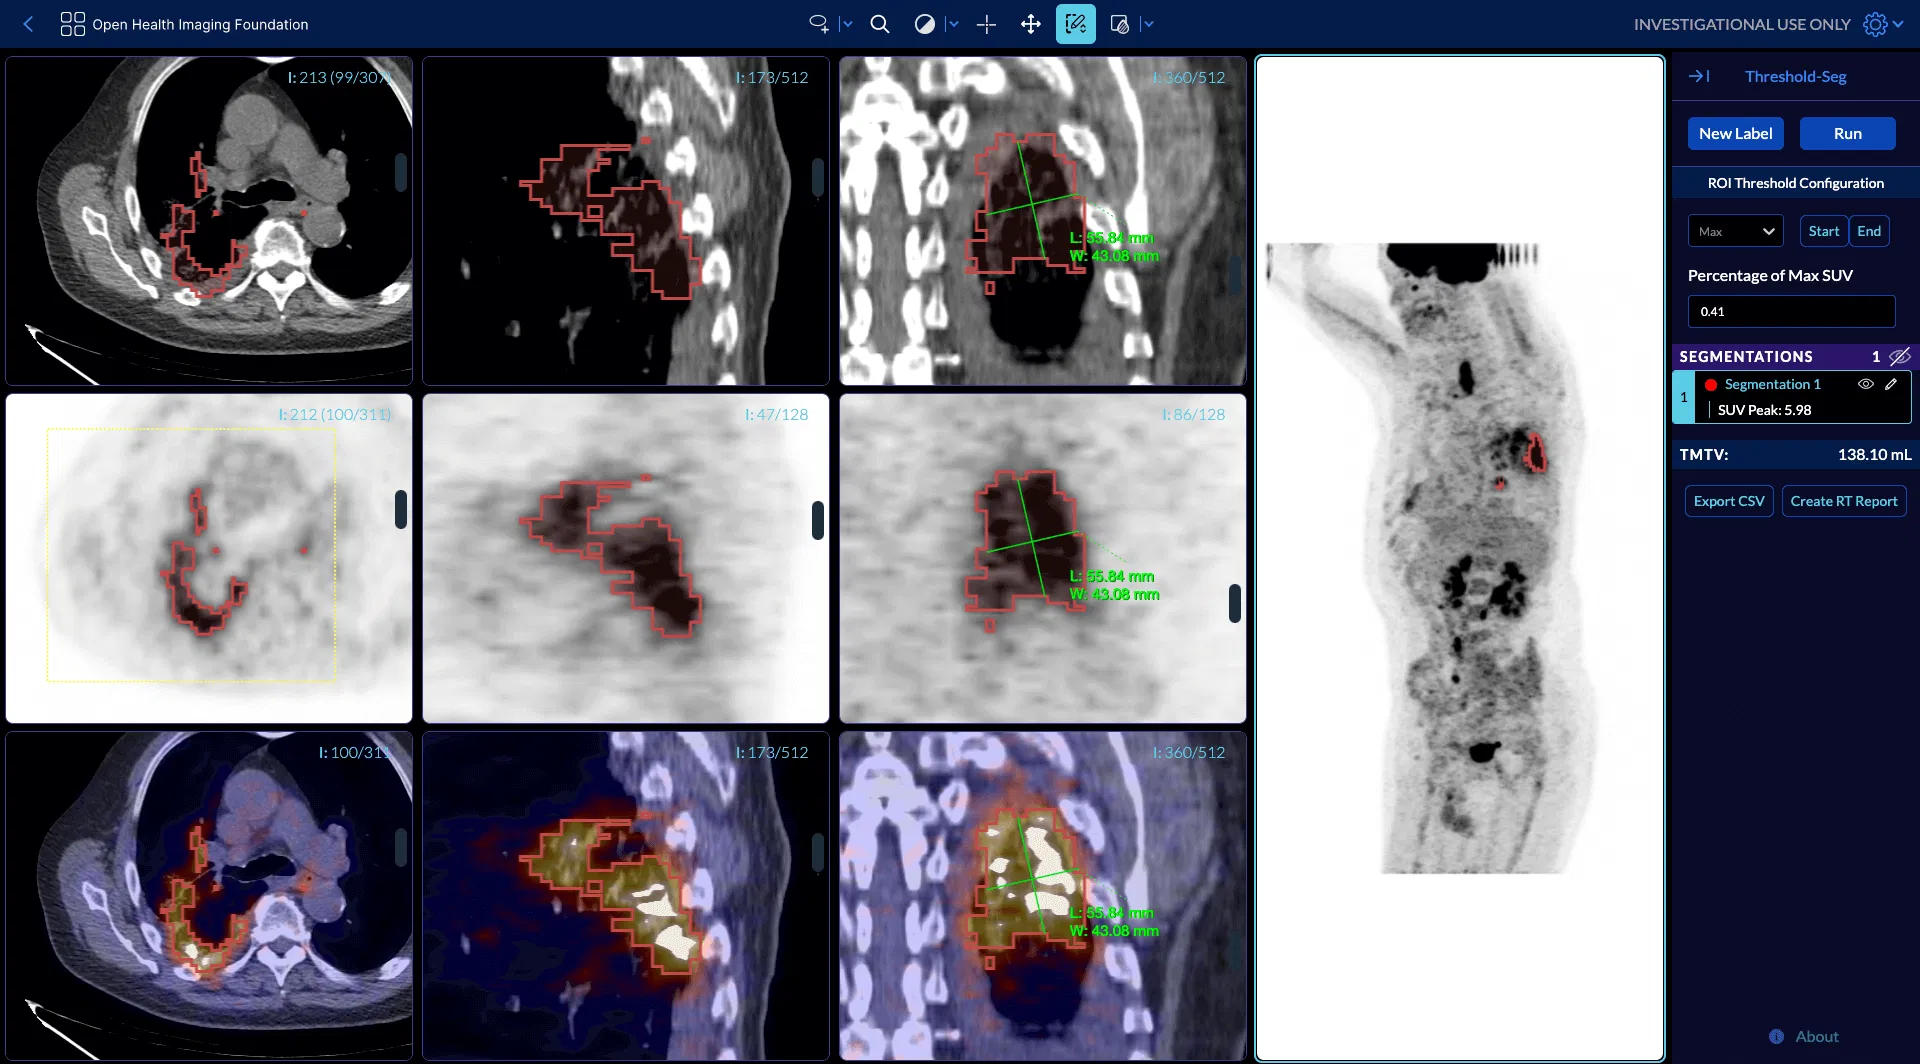

How does OHIF do this? It registers each separate workflow at its own route within your application. Each of these routes encapsulates the specific set of image loaders, layouts, rendering engines and tools that make sense for that kind of image data. For instance, you can have a Microscopy workflow and tools at `/microscopy` while a completely different use case of Total Metabolic Tumor Volume workflow can be accessed at `/tmtv`. Then, when expanding a study in the study list, all available modes show up as buttons where only the modes applicable to the selected study show as active and clickable.